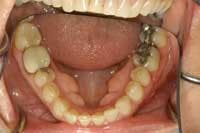

I have read many articles in dental periodicals that often are accompanied by poor-quality images. An obvious example of this is in the use of full-arch mirror images without using lip retractors. It isn’t always easy to acquire images during dental procedures, but it only requires a few more seconds to move the patient’s lips out of the picture (see figures 1 and 2). These images illustrate proper retraction while using an occlusal mouth mirror for full-arch shots.

Another frequent observation is that images are reversed either horizontally or vertically with respect to the desired orientation. This may be caused by an error on submission of the original photos or an error by the publisher. Patients see things so much differently than we do as dentists. When presenting treatment to the patient, it’s more advantageous to orient the images as if the patient is looking into a mirror (see figures 3 and 4). This manipulation is simple with software such as ThumbsPlus and Image FX. Just as in fine restorative dentistry, paying closer attention to details can prevent these simple mistakes.